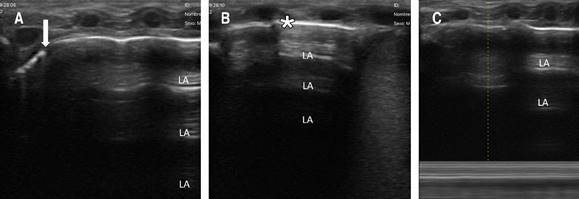

Se procede a realizar UP, como parte del protocolo SAFE,1 observando en la región medial y basal derecha la presencia de neumotórax (Figura 1); mientras que en la región lateral derecha y en el hemitórax izquierdo no se identificaron anormalidades. Cabe señalar que el neumotórax no era visible en la radiografía anteroposterior de tórax, por lo que se solicita radiografía lateral en la cual sí se evidencia el neumotórax anterior (Figura 2).

Figura 1: Se realiza ultrasonido pulmonar (ultrasonido portátil lineal de 10 Hz) observando: A) pulmón anterior apical derecho con presencia de “punto pulmonar” correspondiendo al punto de transición entre un área no deslizante y otra deslizante (flecha). B) Pulmón anterior basal derecho, se observa ausencia del deslizamiento pleural [línea pleural (*) sin movimiento normal en vaivén], con patrón de líneas-A (LA) y ausencia de líneas-B. C) Pulmón anterior medial derecho en modo-M se observa el “signo del código de barras” confirmando ausencia de deslizamiento de la línea pleural.